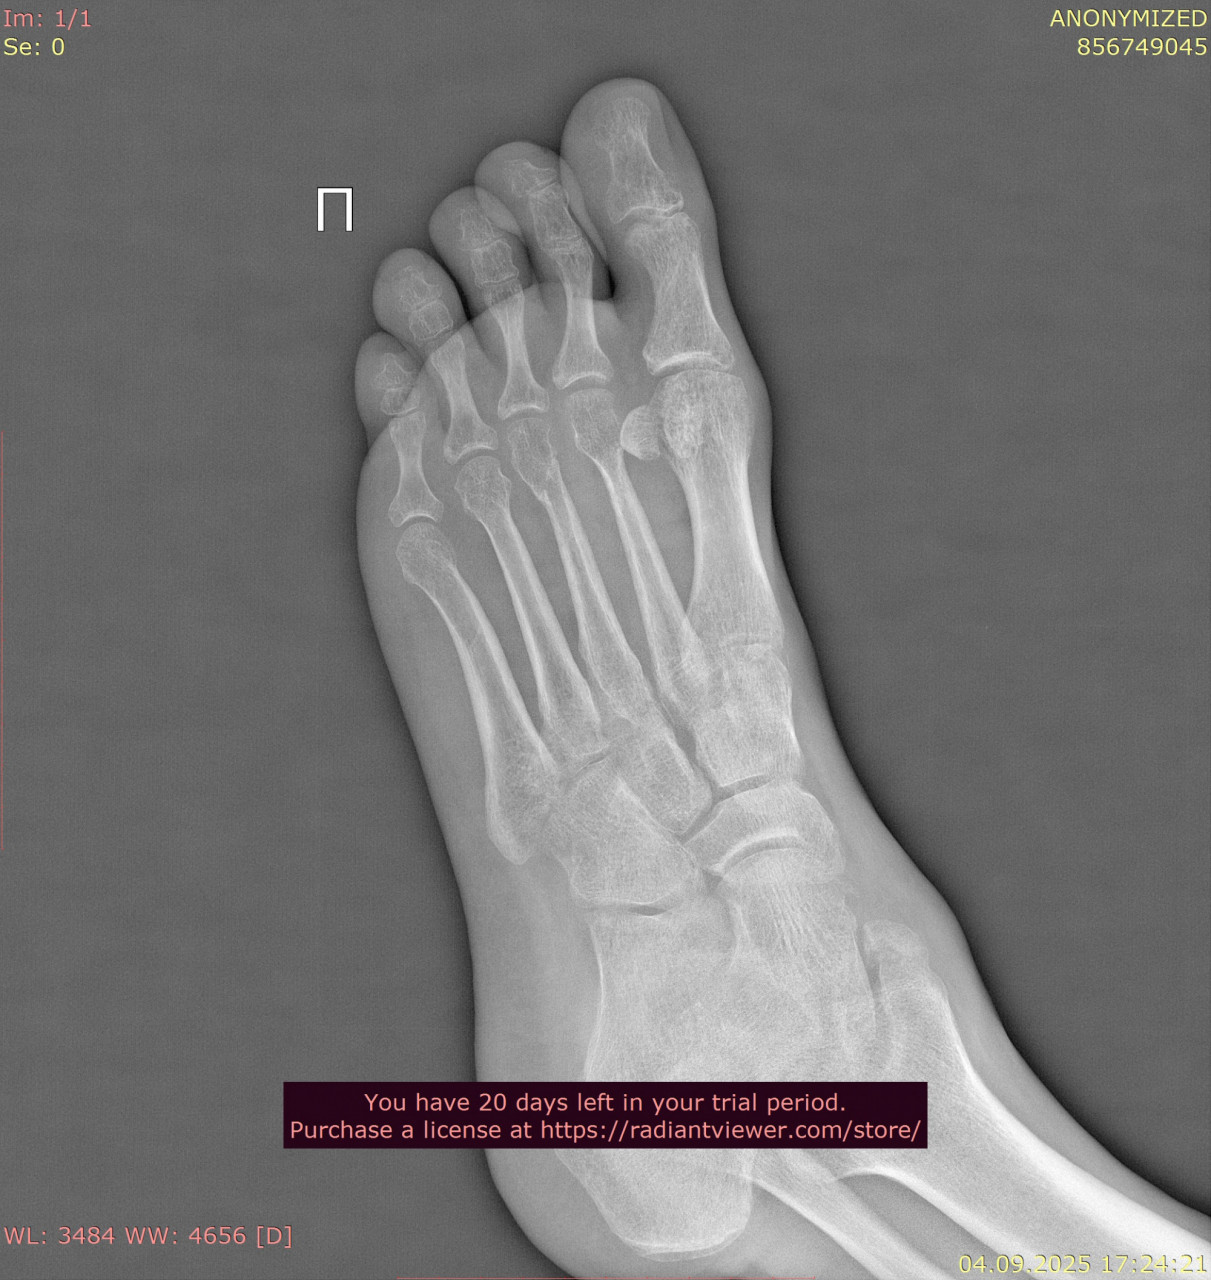

Посмотрите, пожалуйста, снимки стопы от 23.06.2025, когда был перелом, и спустя почти 11 недель от 04.09.2025. Как Вы считаете, переломы срослись нормально, или есть необходимость сделать еше один рентген в будущем? Можно ли переходить к обычному режиму нагрузок? У меня есть еще вторая проекция от 23.06.2025 и снимки голеностопного сустава, там тоже был перелом, но лимит сайта 3 файла. Остальные файлы могу прикрепить к Вашему ответу.

Здравствуйте. Судя по срокам и динамике на снимках, перелом срастается удовлетворительно, костная мозоль сформирована и переходить к постепенной нагрузке можно, но окончательное решение и необходимость повторного рентгена определяет ваш лечащий травматолог с учётом клиники и остеопении.